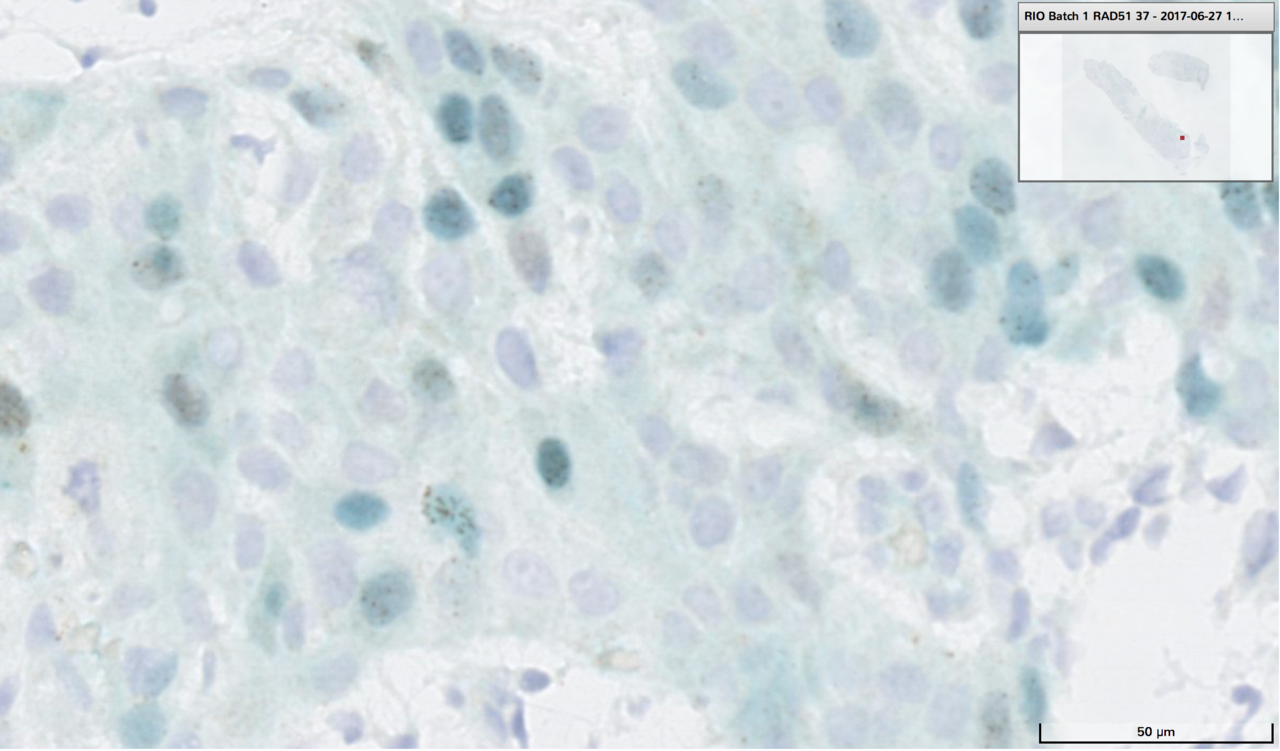

We used targeted and whole genome sequencing to detect underlying mutations of BRCA1/2PALB2 genes, and gene promoter hypermethylation of BRCA1 and RAD51C in TNBC. In collaboration with Serena Nik-Zainal’s lab at The Sanger Institute and Cambridge University, we used the HRDetect assay7, an aggregate of mutational signatures and chromosomal instabilities, to identify HR deficiency. To confirm whether HRDetect had functional implications for tumours, identifying them as susceptible to PARP inhibition, we developed a novel RAD51 immunohistochemistry assay, and found a striking correlation confirming HRDetect identifies cancers with a functional HR defect.

In the current clinical environment, a tissue biopsy is the gold standard to obtain information on a tumour and to guide treatment. However, it can cause pain and discomfort and is resource intensive. Furthermore, Gerlinger et al published a pivotal study detailing intratumour heterogeneity and the underrepresentation of an entire tumour by a single biopsy, challenging the convention of how we monitor cancer response and identify biomarkers8. Circulating tumour DNA (ctDNA), a non-invasive tumour biomarker, is released by tumour sites into the blood and offers a more complete assessment of the patient’s disease, and allows for serial sampling throughout the course of treatment9,10. Early changes in ctDNA dynamics represents an early biomarker of drug activity11–13. In the RIO trial we identified somatic mutations and designed personalised digital PCR assays for each patient to track changes in ctDNA before and after treatment. There was a substantial proportion of patients who suppressed ctDNA after treatment with rucaparib, enriched with HR deficient tumours, assessed by lack of RAD51 foci formation, high HRDetect scores and associated genetic aberrations.

Figure 1. Identification of homologous recombination (HR) deficiency in triple negative breast cancer (TNBC) using functional (RAD51 IHC), genetic (HRDetect) and epigenetic (methylation) analyses allows treatment with targets agents such as PARP inhibitors. Assessment of treatment response can be determined by early changes in circulating tumour DNA (ctDNA) dynamics.